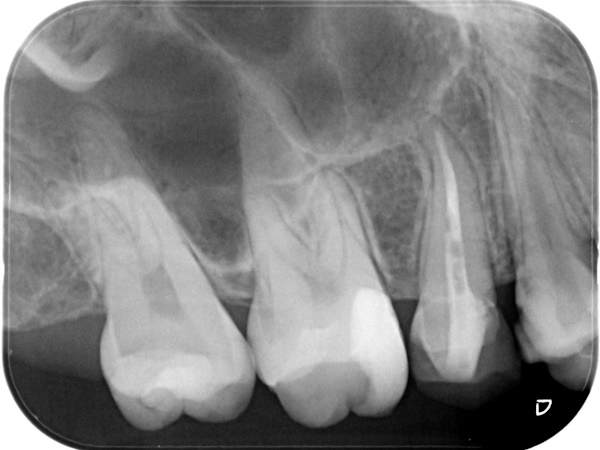

初診時